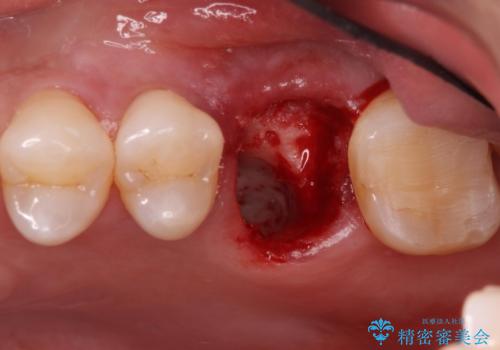

- 左上の奥歯を何とか保存していた患者様です。

今回、残していた歯根から歯茎が大きく腫れ、長期的な予後を期待できないことを考慮し、抜歯してブリッジでの治療を行いました。